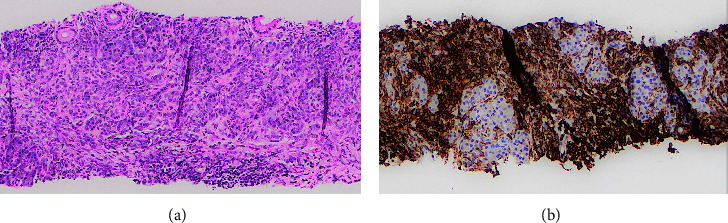

髓系肉瘤(MS)是急性髓系白血病(AML)的髓外表现,通常发生在淋巴结、皮肤、软组织和骨骼等部位。在胰腺中的表现更为罕见,自1987年以来,文献报道的病例不足20例。尽管 MS 很罕见,但在鉴别诊断引起阻塞性黄疸的软组织肿块时应考虑 MS,尤其是当患者患有已知的血液病时。已知胰腺多发性硬化的孤立病例可发展为急性髓细胞性白血病;因此,将多发性硬化与胰腺癌或胰腺炎等更常见的诊断相鉴别至关重要。这是一例 70 岁男性因胰腺多发性硬化继发症状性梗阻性黄疸的病例,最终需要通过内镜超声(EUS)和内镜逆行胰胆管造影(ERCP)进行诊断和治疗。该报告还全面回顾了以往类似胰腺多发性硬化症的临床表现、管理和治疗的病例报告。

Myeloid sarcoma (MS) is an extramedullary manifestation of acute myeloid leukemia (AML) and commonly occurs in sites such as the lymph nodes, skin, soft tissues, and bone. It more rarely manifests in the pancreas, with less than 20 cases reported in the literature since 1987. Despite its rarity, MS should be considered in the differential diagnosis of a soft tissue mass causing obstructive jaundice, especially if the patient has a known hematologic disease. Isolated cases of pancreatic MS have been known to progress to AML; therefore, it is crucial to differentiate MS from more common diagnoses, such as pancreatic cancer or pancreatitis. This is a case of a 70-year-old male with symptomatic obstructive jaundice secondary to pancreatic MS, ultimately requiring endoscopic ultrasound (EUS) and endoscopic retrograde cholangiopancreatography (ERCP) for diagnosis and management. Also included is a comprehensive review of previous case reports with similar clinical presentations, management, and treatment of pancreatic MS.